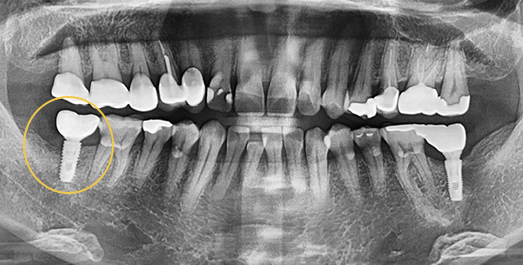

Implant Revision Surgery

Revision implant surgery is more challenging

and complex than the original procedure

Improper implant surgery or inadequate implant maintenance can lead to complications accompanied by pain. Implant revision surgery involves removing the existing implant, rebuilding the alveolar bone, reshaping the gingival contour,

and placing a new implant in the correct position.

An implant placed at another clinic was found to be significantly mispositioned,

requiring revision surgery to correct the placement to the proper position.